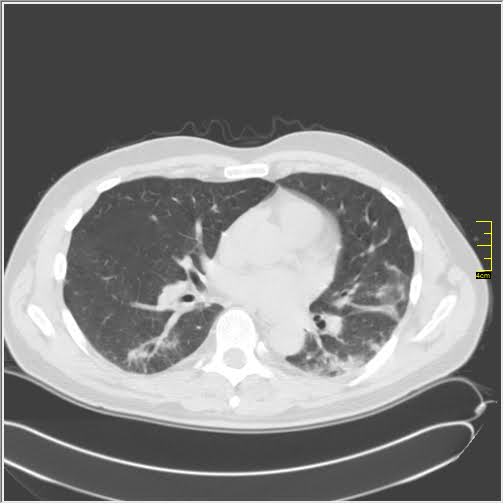

CT nalazi kod kovida-19

Vraćam se na svoju usku struku (da ne bude da se mešam u tuđu). Kompjuterizovana tomografija, skener ili CT je metoda pregleda koja je superiorna kod zapaljenskih bolesti pluća. Kod kovida-19 se pokazala kao nezamenjiva u diferencijaciji u odnosu na ostale bolesti. Tačnost nalaza na plućima je visoka.

- Ground glass konsolidacije (GGO). To su one bele "mrlje" na snimcima koje su karakteristične za ovu bolest. Nazivaju se "ground glass" svuda. Izgledaju kao da se taj deo pluća gleda kroz mlečno staklo, kao neka vrsta mikromozaika

- Crazy paving. To su linearna zadebljanja koja se nekada vide u ground glass konsolidacijama. Ona nastaju kasnije, ne javljaju se pre GGO. Neko ih opisuje kao da pijani majstori slažu pločice. Na slikama se to vidi kao nepravilna zadebljanja unutar GGO, složena bez ikakvog reda

- Vaskularne dilatacije. Dolazi do zapaljenskog procesa krvnih sudova i/ili do zastoja tako da su nam na snimcima krvni sudovi "deblji".

- Trakcione bronhiektazije. To su proširenja vazdušnog prostora (ali ne onog koji učestvuje u disanju) koja nastaju kada stradaju alveole i proširuje se prostor između njih

- Arhitektonske distorzije. Pojava traka blizu pleure koje nastaju propadanja plućnog tkiva i nastanka fibroznog.

Svaki od ovih znaka se može javiti i kod drugih bolesti ali svi zajedno su specifični za kovid-19

Da bi objasnili stanje koristimo Severity Score. On služi za procenu ozbiljnosti bolesti. Pluća se sastoje od pet lobusa. Procenjuje se svaki pojedinačno ocenama od 0 do 5. To znači da se skor kreće od 0 do 25.

Na CT razlikujemo 4 faze (najčešće ali nije decidirano tako)

Rana faza (0 do 4. dan) - pojedinačne GGO, neka crazy paving, nizak skor

Progresivna faza (5. do 8. dan) - povećanje broja GGO i crazy paving

Pik faza (10. do 13. dan) - javljaju se konsolidacije pluća, to znači da veliki delovi pluća izgledaju kao velike bele površine a označavaju delove pluća koji su masa koja koja je u celini zahvaćena zapaljenskim procesom

Faza rezolucije (posle 14. dana) - vraćanje delova pluća u normalu ili smrt

Iskustveno smo došli do skora 15 koji predstavlja neku granicu između verovatno dobrog i verovatno lošeg ishoda. Samo tumačenje zavisi od faze bolesti. Naš nalaz je samo deo procene i ne menja laboratorijske i pulmološke, kao ni ostale. Svaki nalaz zajedno daje ukupnu sliku bolesti.